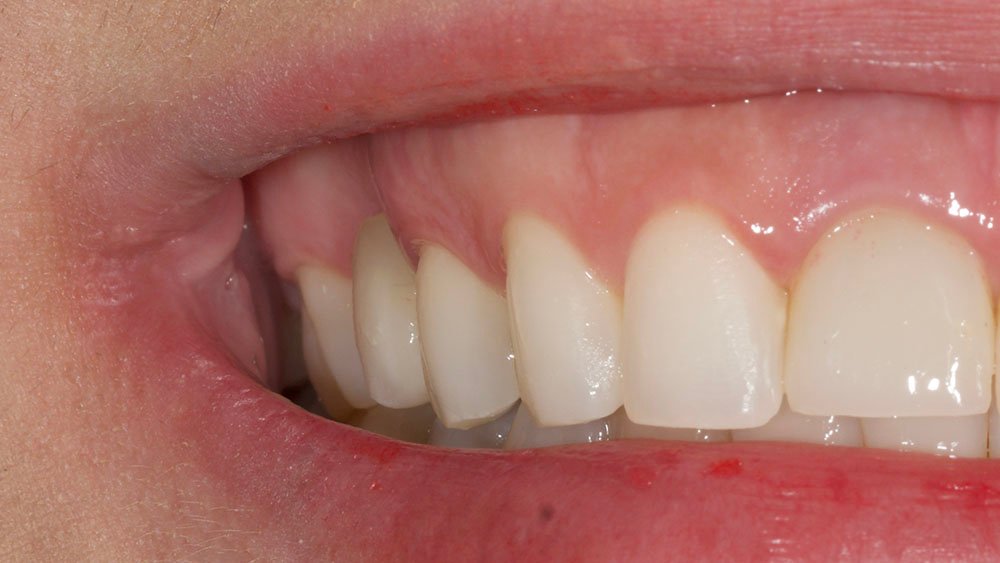

Para este relato de caso clínico selecionou-se a paciente A. S. P, do gênero feminino, de 22 anos, que procurou a Clínica de Especialização em Implantodontia devido a uma perda dentária do elemento 15 por trauma, culminando como queixa principal a ausência do elemento dental e a gengiva aprofundada.

Durante a anamnese, a paciente apresentou um bom estado de saúde geral e não relatou nenhum dado médico relevante que impossibilitasse o tratamento. No exame físico intraoral, observou uma boa condição de saúde bucal, notando-se apenas a ausência do elemento 15 com uma depressão óssea no vestibular. Dessa forma, objetivou-se um plano de tratamento baseado na utilização da técnica de rolo modificada e colocação de dente provisório.

O procedimento selecionado para esse relato de caso promoveu resultados satisfatórios e melhorou a estética. No término do procedimento cirúrgico, a paciente foi orientada a tomar uma cápsula de Amoxicilina 500 mg (EMS – Germed Farmacêutica, São Paulo- Brasil) a cada 8 horas por sete dias; um comprimido de Nimesulida 100 mg (Eurofarma Laboratórios S/A, São Paulo-Brasil) a cada 12 horas por três dias; e um comprimido de Dipirona 500 mg (Sanofi Medley Farmacêutica Ltda., São Paulo-Brasil) a cada 6 horas. Além disso, foi indicado à paciente que evitasse alimentos pastosos e pegajosos, que preferisse alimentos frios ou gelados e utilizasse bolsa de gelo no local.

No acompanhamento mensal realizou-se proservação e radiografias periapicais da região para verificar a cicatrização dos tecidos e integridade do implante. Após o período de três meses, foi cimentada uma coroa definitiva de zircônia monolítica.